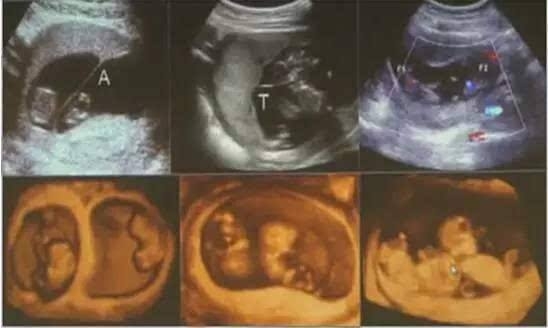

我们在第一时间为郑女士办理了住院,入院孕周35+4周,在产科主任于慧的带领下,产科一区诊疗组对郑女士的病情进行了全面而详细的评估和分析,经评估判断,该孕妇系单绒毛膜性双胎妊娠,由于两胎儿共同一个胎盘,胎盘之间存在血管吻合,故可以出现较多且较严重的并发症,其中比较严重的有双胎输血综合征和选择性胎儿生长受限,围产儿发病率和死亡率均增加,但若马上手术娩出胎儿,考虑新生儿为早产儿,住院几率大,并发症多,费用高,预后差等风险,真是两难抉择!

随着近年辅助生殖技术的广泛开展,双胎妊娠发生率明显增多,双胎妊娠属于高危妊娠,易引起妊娠期高血压疾病、妊娠期肝内胆汁淤积症、贫血、胎膜早破及早产、产后出血、胎儿发育异常等并发症。单绒毛膜双胎还可能合并双胎输血综合征、选择性胎儿生长受限等特殊并发症,故在妊娠早期需进行双胎妊娠的绒毛膜性的判断,这为分娩时机的确定奠定基础。我院年分娩量在浙南地区名列前茅,技术力量雄厚,新生儿科、麻醉科等相关科室团结协作,对双胎妊娠的孕期管理及处理流程有着丰富的临床经验,并已形成一整套规范的流程,使每一位双胎妈妈都能得到及时诊治,在充满爱心、耐心、责任心的服务中,迎接新生命的到来。